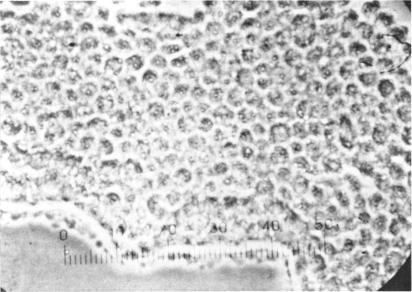

Three major pathologic processes caused by light in the primate retina: a search for mechanisms.

Trans Am Ophthalmol Soc. 1982;80:517-79.